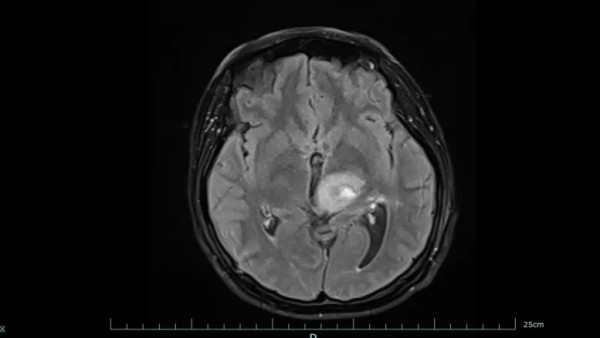

左为治疗前,右为治疗后。图片来源于稿源单位

好在经过系统治疗,黄女士的肿瘤明显缩小,病情得到有效控制。目前,她已回归正常生活和工作,生活质量显著改善。